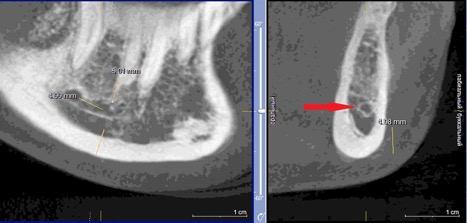

При измерении расстояния от резцовой петли до вестибулярной стенки нижней челюсти и её топографии в области правила «трёх пятёрок», выделено три положения канала, в котором проходит резцовая петля: канал прилежит, т.е. стенка канала образована кортикальной частью (рис 3), касается, т.е. имеет одну общую точку (рис 4) и не имеет общих точек.

Рисунок 3. КЛКТ Сагиттальныи и коронарныи реформаты переднего отдела нижнеи челюсти..jpg

Рисунок 3. КЛКТ Сагиттальный и коронарный реформаты переднего отдела нижней челюсти.

Стенка канала образована кортикальной частью кости.

Красная стрелка – «резцовая петля».

Красный пунктир – канал проходит в проекции участка правила «трёх пятёрок».